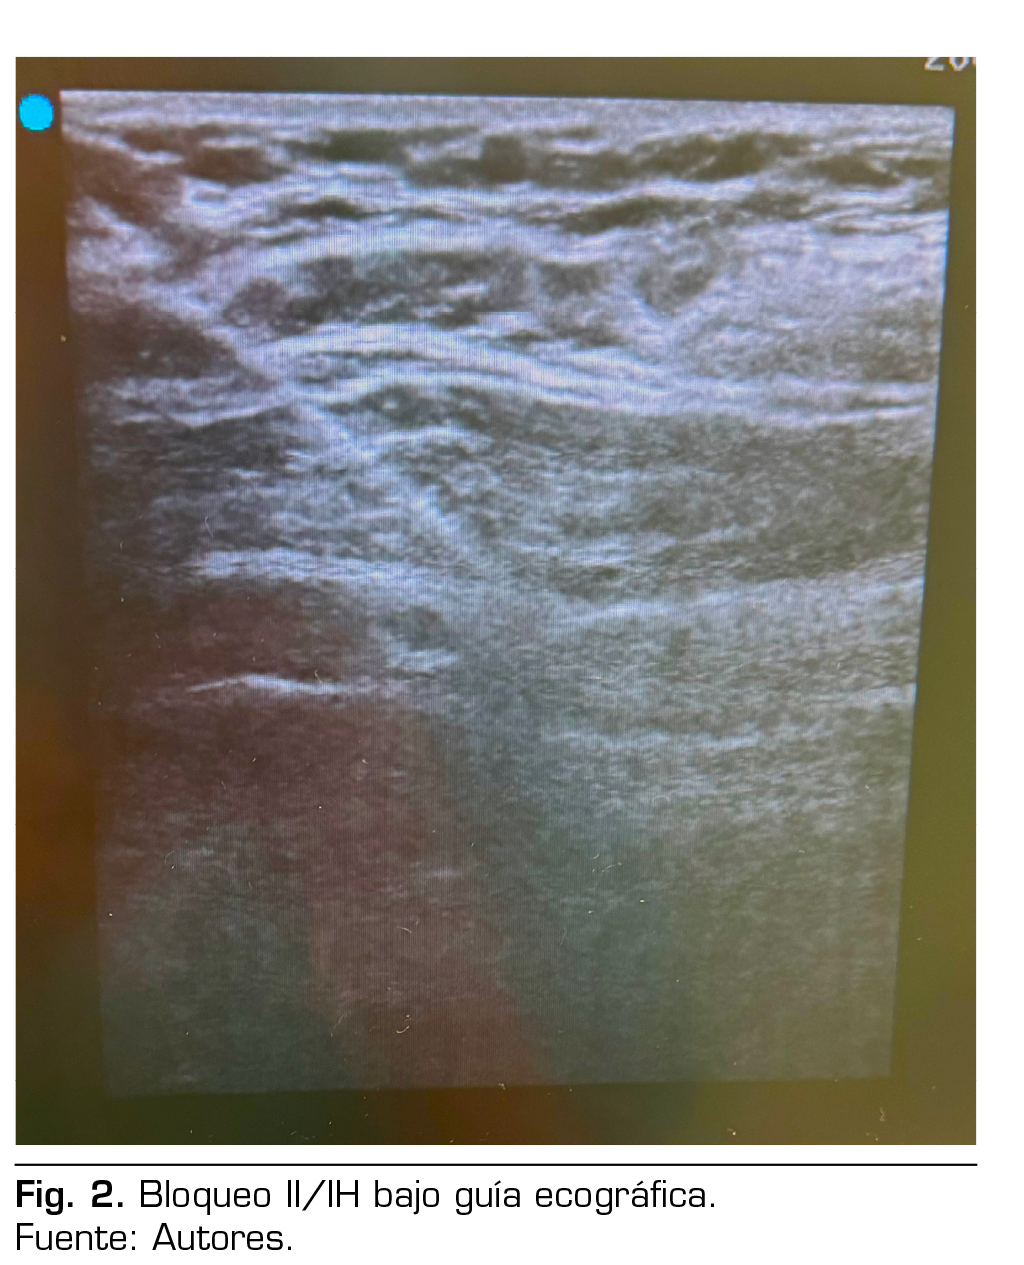

Presentación de caso: Presentamos el caso clínico de un paciente adulto mayor de 88 años ASA III, sometido a una hernioplastia inguinal electiva, bajo anestesia regional: bloqueo II/IH bajo guía ecográfica más sedación, manejo analgésico complementario con paracetamol y antinflamatorios, alta de cirugía médica ambulatoria a su domicilio y control postoperatorio sin complicaciones.

Figura 2